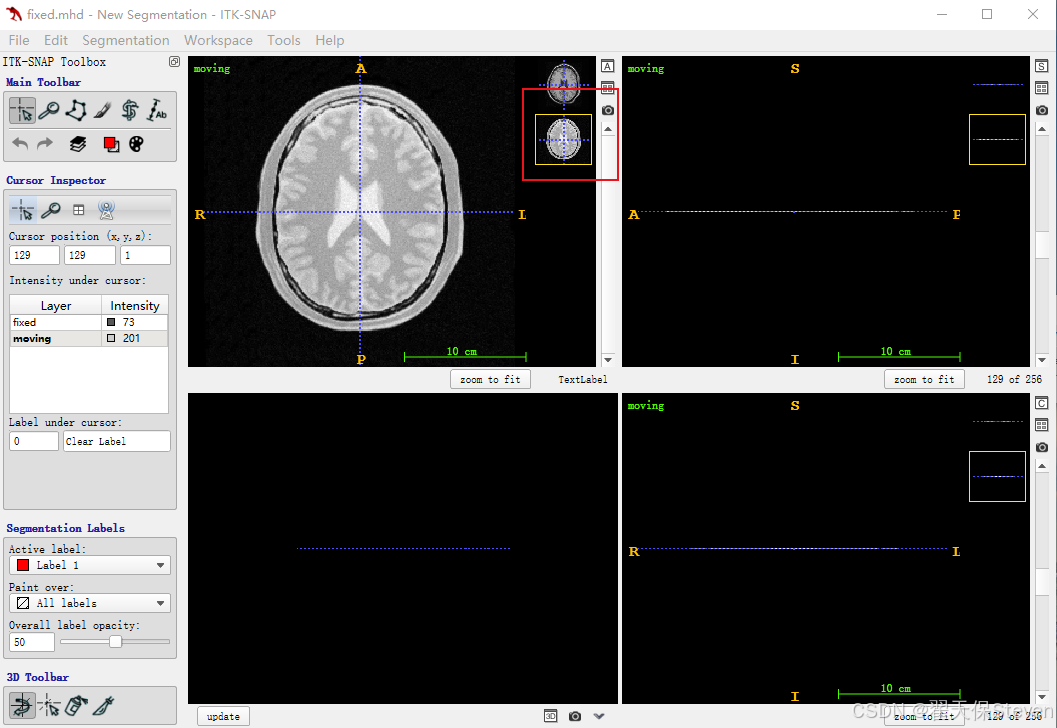

4)点击File,点击Add Another Image,加载moving.mhd,如下所示。

5)在第二张图右上角有个箭头,点一下,选择Display as overlay,会发现第二张图像和第一张图像融合在一起了。